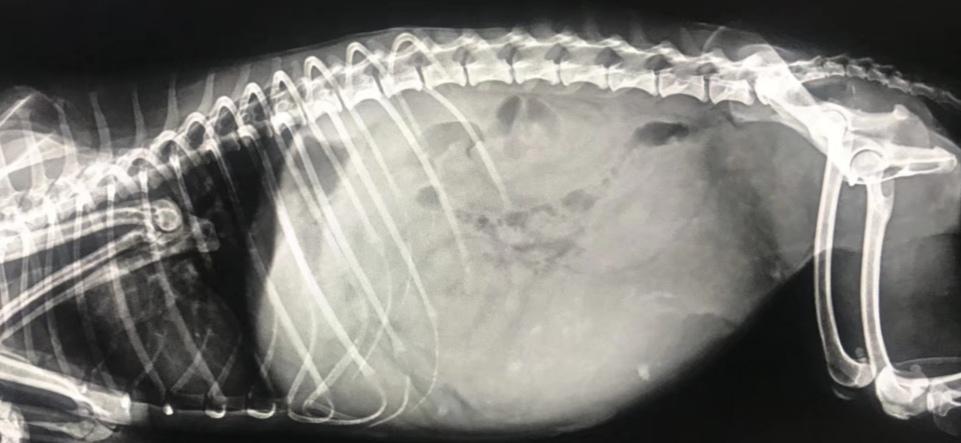

一只2岁的狗狗竟然患上子宫蓄脓,手术摘下蓄脓的子宫,看着让人害怕。

Lili察觉到不对劲,于是带去医院一检查,竟然被告知狗狗患有闭合性子宫蓄脓。

闭锁性的子宫蓄脓, 是指子宫完全关闭,经母狗阴门处流不出来脏的分泌物,只能蓄积在子宫里面,使子宫越来越大,腹围也跟着增大。